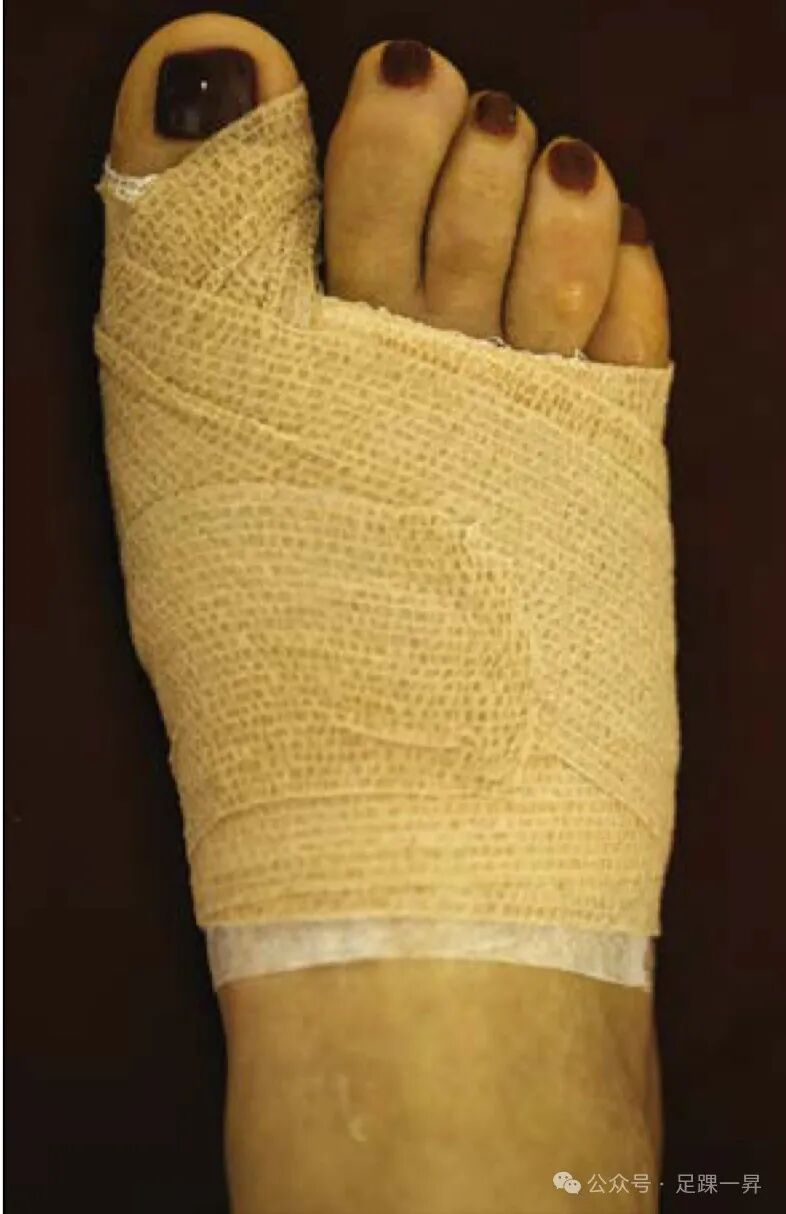

▲拇外翻术后的经典包扎方法。